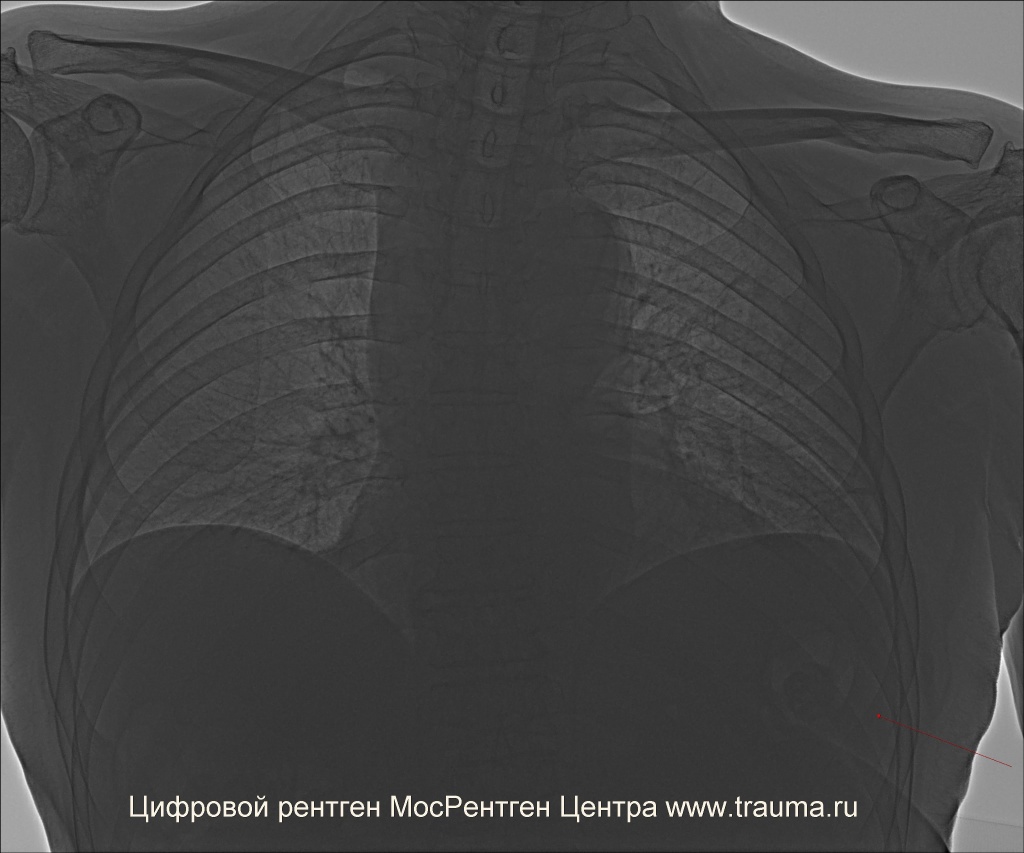

Другой пациент весом около 160 кг. На обычном режиме не видны нижние отделы легких.

Пульсоксиметр: 96%, ЧСС 76 в минуту, ЧДД 16 в минуту.

Пациент повышенного питания.

Проекции исследования: прямая задне-передняя проекция.

Положение пациента: сидит на кровати.

ЭЭД: 0.2 мЗв.

Качество снимков: удовлетворительное.

Легочные поля: без очаговых и инфильтративных изменений.

Легочный рисунок: не изменен, усиление интерстициального компонента. В верхних долях легких, больше слева, отмечается исчезновение сосудистого рисунка, особенно в дистальных частях.

Корни легких: не расширены, структурны.

Синусы: свободны с обоих сторон.

Плевральная полость: газ не определяется.

Апикальная плевра: не изменена.

Междолевая плевра: не изменена.

Диафрагма: обычно расположена. Справа - уплощена.

Сердце: без заметного увеличения отделов.

Аорта: без особенностей, кальциноз.

Тень средостения: не расширена, не смещена.

Контуры трахеи усилены.

Костная система: костная плотность снижена.

Заключение: Двусторонняя эмфизема. Пневмосклероз?

При 6 мАс можно увидеть все легочные поля. При выравнивании плотности все равно заметно отсутствие легочного рисунка, особенно в верхушке левого легкого.